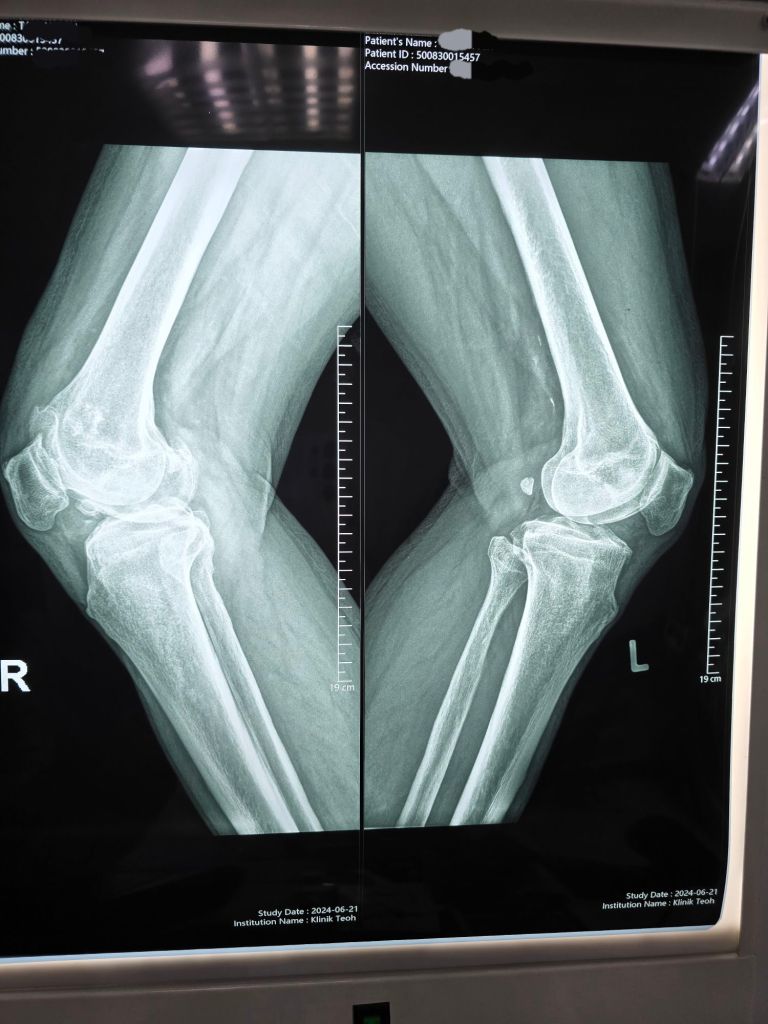

Diagnosis

Recent X-rays revealed advanced osteoarthritic changes in the right knee compared to the left, highlighting the severity of the degeneration.